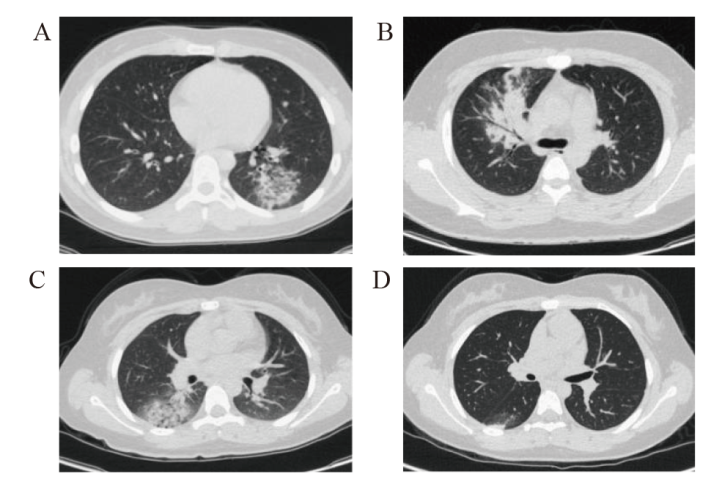

温潇慧, 李惠民, 张晓艳, 等. 儿童肺炎衣原体肺炎10例临床特征分析[J]. 中华儿科杂志, 2025, 63(4): 362-366.

Wen XH, Li HM, Zhang XY, et al. Clinical features of Chlamydia pneumoniae pneumonia in 10 children[J]. Zhonghua Erke Zazhi, 2025, 63(4): 362-366.